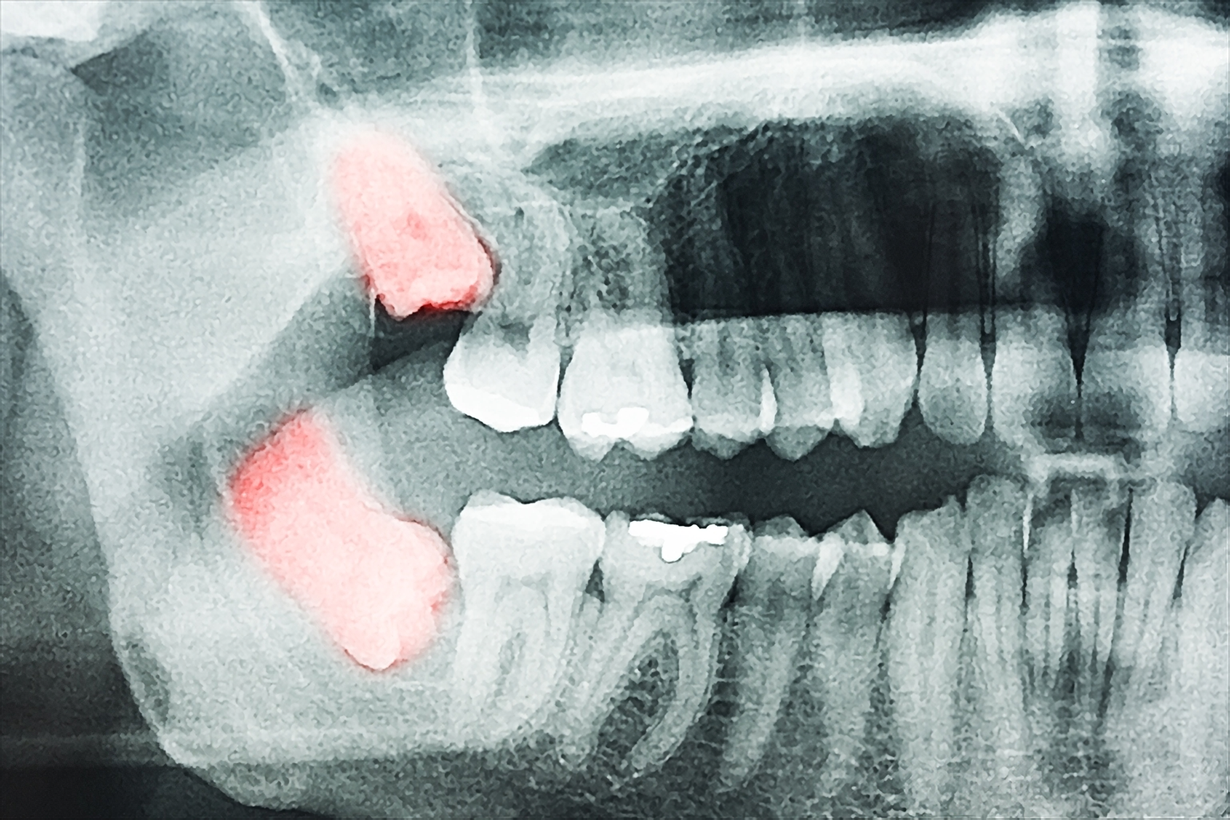

石井デンタルクリニックでは、横向きに生えている親知らずや、歯ぐきに埋まっている親知らずの抜歯にも対応しています。症状に応じて、より専門的な処置や高度な設備が必要な場合には、大学病院への紹介も行える体制を整えています。

治療の前には、歯科用CTなどの精密機器で顎の状態を立体的に把握し、より安全で正確な手術計画を立案します。治療中の痛みを抑える麻酔や術後の鎮痛処理にも万全を期しており、患者様が安心して治療を受けていただける環境を整えています。

傷ついた歯や折れたあごの骨の治療、口腔内の腫瘍や膿瘍が見つかった場合も、適切な処置を行います。損傷を受けた歯や骨を放っておくと機能障害を起こすことがあるので、早めの受診をおすすめします。